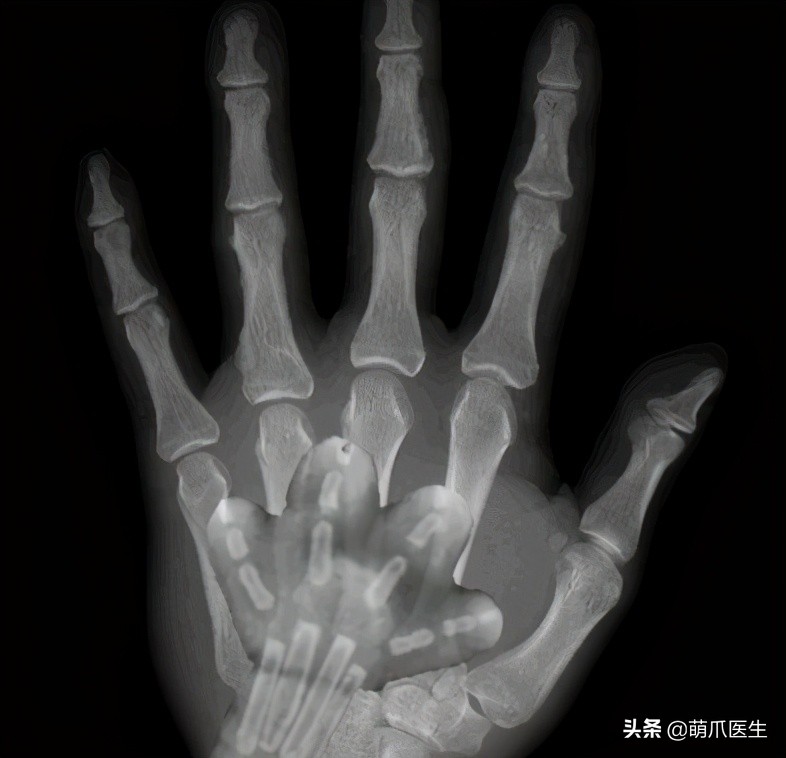

猫爪X光片实则来自这张在网上盛传已久的图片。

故事的主角猫爪X光片,其实是七年前一位国外网友LinzerBinzer发布的。

当时,他捡到了一只腿被卡在树枝里的小猫。 送去医院检查后,兴奋的他第一时间把照片分享到了网上:

大家绝对没见过这么可爱的X光片!

因为画风实在太逗了,照片引起了无数网友的尖叫转发。

但很快,质疑出现了。有的网友认为 X光片里猫咪的骨头太少了,并不像真实的猫爪。

有经验的网友还贴上了自己家猫的X光,表示猫爪分明长这样啊!

为了证明自己没有作假,LinzerBinzer不得不上传了小猫咪另一只脚的X光片,看上去确实是同样的效果……

另一部分支持LinzerBinzer的网友则帮他解释说:

小猫年龄只有5~6周大,骨骼系统还没有完全发育。此时它骨头之间相连的结缔策划在X射线下是透明的,所以看上去才会如此“不真实”。

一派认为,猫咪X光大概率是假的。无论从比例还是骨头结构上来看,它都不是正常猫爪该有的样子。

另一派则认为,从细节上看,这是真实的X光片。 成像如此是因为幼猫骨化不完全。

但可以明确的是,猫咪骨骼发育完全时,爪爪的X光片绝对就长这样: